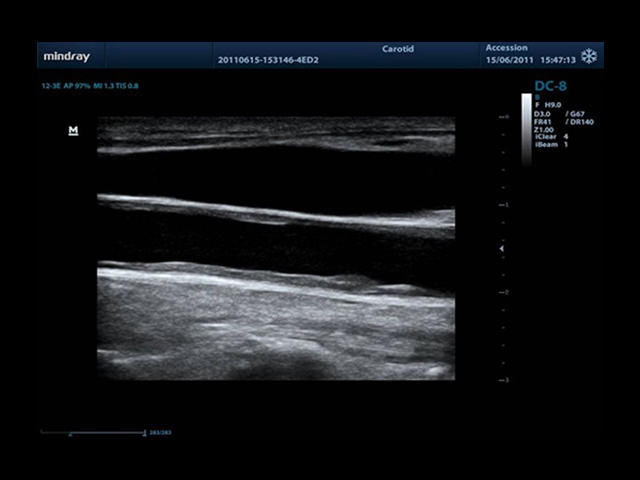

Mindray DC-8 Exp – это ультразвуковой аппарат с архитектурой mQuadro и функцией эластографии Natural Touch. Он оснащен высококлассным 21-дюймовым TFT-монитором с разрешением Full HD. Данный аппарат представляет интерес для специалистов, занимающихся обследованием мягких тканей с использованием эластографии. Режим объемного 4D-сканирования позволяет получать максимально точные диагнозы, сокращая количество неэффективных процедур.

Mindray DC-8 Exp оснащен новым поколением датчиков с увеличенным количеством элементов и инновационной технологией "3T". Это позволяет достичь высокой детализации и качества изображения. Благодаря новейшей технологии iFlow, можно визуализировать даже самые мелкие сосуды и кровеносные пути.

Сверхширокополосная нелинейная обработка изображений снижает визуальные шумы на 30% по сравнению с другими системами. Технология iClear позволяет устранить зернистость изображения, а iBeam (технология пространственного компаундинга) обеспечивает высокое качество сканирования органов и тканей под различными углами.

• Auto IMT Package - измерения и анализ толщины комплекса интима-медиа (КИМ) сонной артерии.